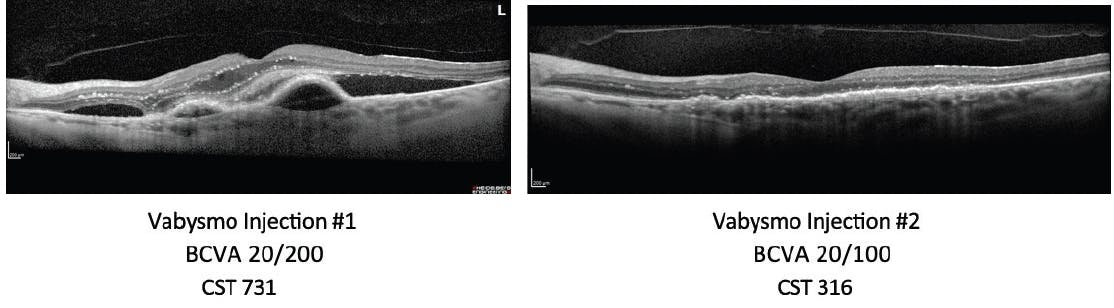

This first case study involves a 79-year-old treatment-naïve patient with a long history of bilateral wet AMD. The patient’s BCVA was 20/200, with a CST of 731 µm, when she received her first Vabysmo treatment. This patient experienced rapid improvement in vision and retinal fluid 1 month after her first Vabysmo injection during the loading dose period (Figure 1). This improvement was maintained over the course of 4 months and the patient’s treatment interval continues to be extended.

Figure 1. OCT scan at 4 weeks post-initial Vabysmo injection shows rapid retinal fluid resolution in a treatment-naïve wet AMD patient.